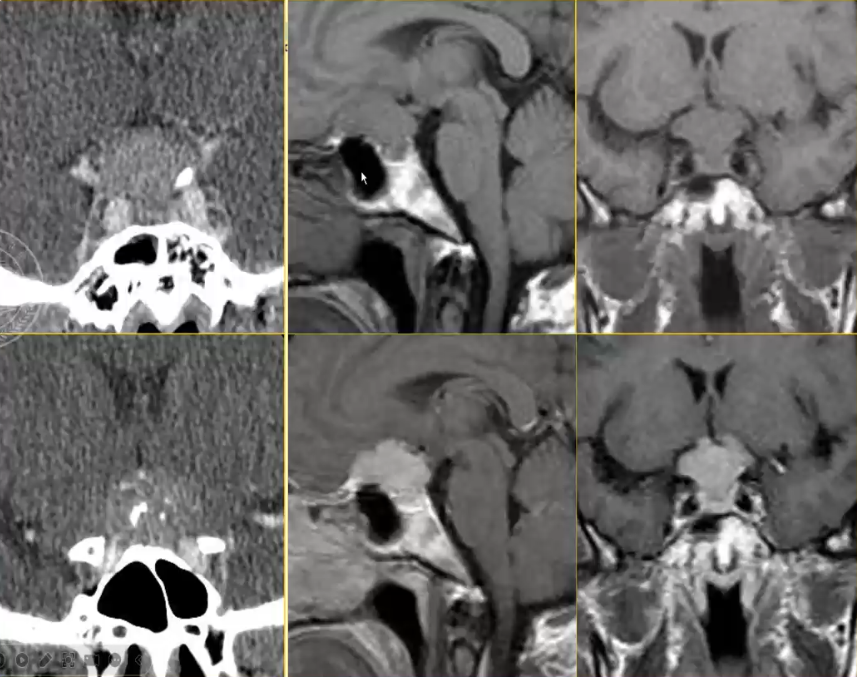

鞍区肿瘤性病变的鉴别诊断

√颅咽管瘤:多为囊性或部分囊性,囊壁多有钙化;囊液成份复杂:胆固醇结晶、普通蛋白质、角蛋白和钙化沉着等。钙化T2为低信号,T1可为低、等、高信号。